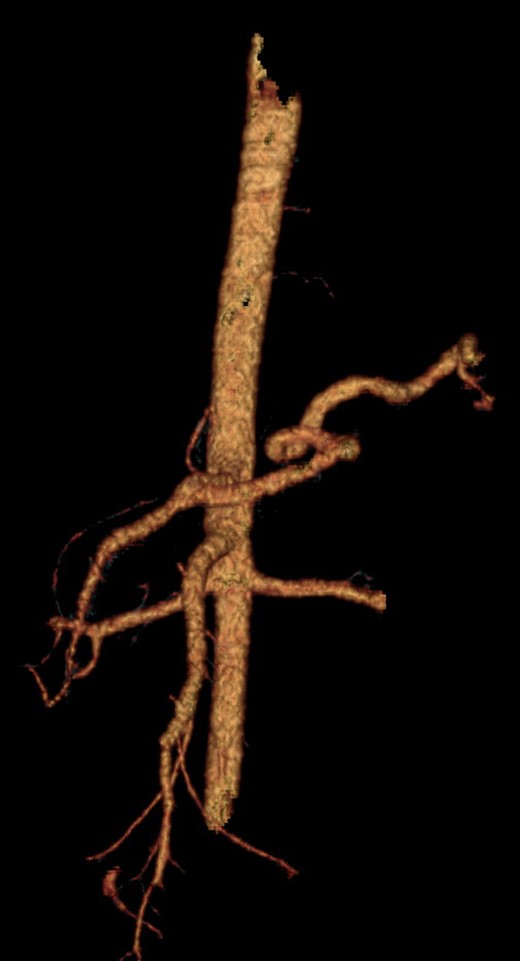

He was admitted to the Resuscitation Unit and after hemodynamic recovery, a CT scan was performed with no neurological lesions, confirming the findings observed intraoperatively as well as the absence of blood flow in the hepatic artery (Fig. 1).